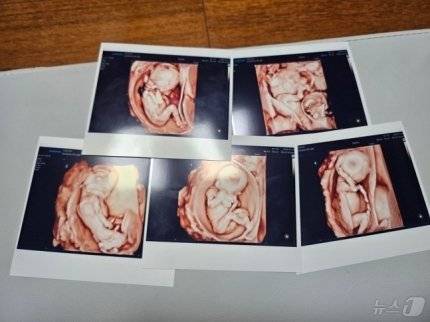

동두천시에 거주하는 김준영·사공혜란 부부는 자연임신으로 잉태된 남자아이 3명과 여자아이 2명을 지난 20일 서울 성모병원에서 건강하게 출산했다. 김씨는 동두천 지역 고등학교 교사로 재직 중이며, 사공씨는 경기 양주의 한 학교에서 교육 행정직으로 근무 중이다. 자연임신으로 다섯쌍둥이가 생겨 건강하게 태어난 것은 국내에서 최초다.